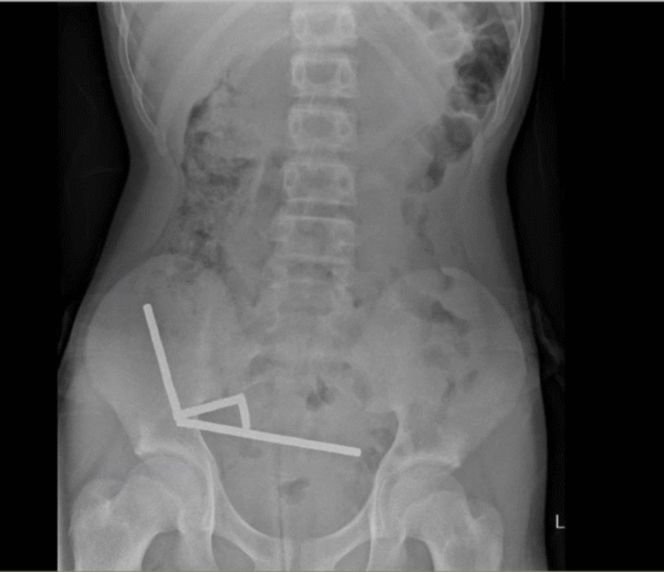

Röntgen görüntülerinde, çocuğun karnının sağ alt kısmında birbirine yapışmış metal yığınları tespit edildi ve çocuğun yaklaşık 100 mini neodyum mıknatıs yuttuğu belirlendi.

Doktorlar, tıkanıklık belirtisi görülmeyen çocuğu daha net inceleme için ameliyata alırken, operasyon sırasında mıknatısların baskısı sonucu bağırsak dokusunda hasar oluştuğunu tespit etti.